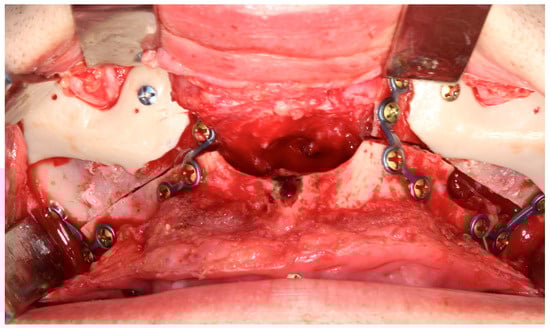

Reconstructing the Head and Neck region presents some of the most complex challenges in surgery, requiring not just technical precision but also creativity, collaboration, and innovation. In recent years, we’ve seen incredible progress thanks to advancements in areas like 3D printing, virtual surgical planning, augmented/mixed reality, artificial intelligence, tissue engineering, and biomaterials. Yet, while the tools at our disposal are more advanced than ever, the challenge remains: how do we translate innovation into better outcomes for our patients?

This Special Issue aims to bring together fresh insights, groundbreaking research, and real-world clinical experiences that are shaping the future of oral and cranio-maxillofacial reconstruction. We welcome contributions that explore novel surgical approaches, digital tools, regenerative techniques, and interdisciplinary strategies that improve both function and aesthetics for patients. Whether you're working at the bench or the bedside, we hope this collection will serve as a platform for sharing ideas that push the boundaries of what's possible in this evolving field.